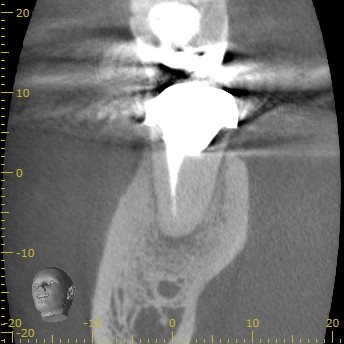

D

遠心根にはほぼ病変はないようだ。

ここは、再根管形成も不要と考えてもいいだろう。

ということで、この歯の治療は再根管治療だ。

そして、

M根のみを攻略すればいいとわかる。

それが、

Selective Root Canal Retreatment

である。